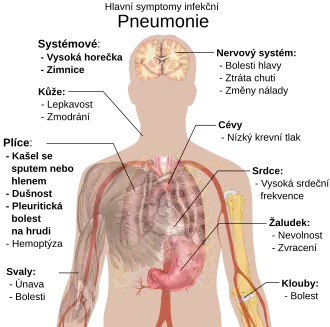

Lidé postižení infekčním zápalem plic často vykazují produktivní kašel, horečku doprovázenou zimnicí, dušnost, ostrou nebo bodavou bolest na prsou při hlubokém nádechu a zvýšenou dechovou frekvenci.[9] U starších pacientů může být nejzřetelnějším příznakem zmatenost.[9] Typické příznaky a symptomy u dětí mladších pěti let pak zahrnují horečku, kašel a zrychlené nebo obtížné dýchání.[10]

Horečka není pro tuto chorobu příliš specifická (vyskytuje se totiž u řady dalších běžných nemocí) a u osob, které trpí závažnou formou nemoci nebo podvýživou, může zcela chybět. Děti mladší 2 měsíců často navíc nevykazují ani kašel.[10] K závažnějším příznakům a symptomům lze počítat promodralou kůži, snížený pocit žízně, křeče, přetrvávající zvracení, extrémně vysoké teploty nebo poruchy vědomí.[10][11]

Jak bakteriální, tak virová pneumonie jsou obvykle provázeny podobnými příznaky.[12] Některé z příčin souvisí s klasickými, avšak nespecifickými klinickými charakteristikami. Pneumonii způsobenou bakterií Legionella může doprovázet abdominální bolest, průjem či zmatenost,[13] zatímco zápal plic vyvolaný streptokokem Streptococcus pneumoniae je spojen s vykašláváním rezavě zbarveného sputa;[14] pneumonie vyvolaná bakterií Klebsiella může být doprovázena vykašláváním sputa krvavého (jež je v anglosaských zemích často označováno jako „rybízový džem“).[8] Krvavé sputum (známé jako hemoptýza) se objevuje i u tuberkulózy, pneumonie vyvolané gramnegativními bakteriemi a plicních abscesů, častěji ale u akutní bronchitidy.[11] Mykoplazmatický zápal plic vzniká v souvislosti s otokem mízních uzlin na krku, bolestí kloubů nebo zánětem středního ucha.[11] Virový zápal plic je doprovázen sípáním častěji než tomu je u pneumonie bakteriální.[12]